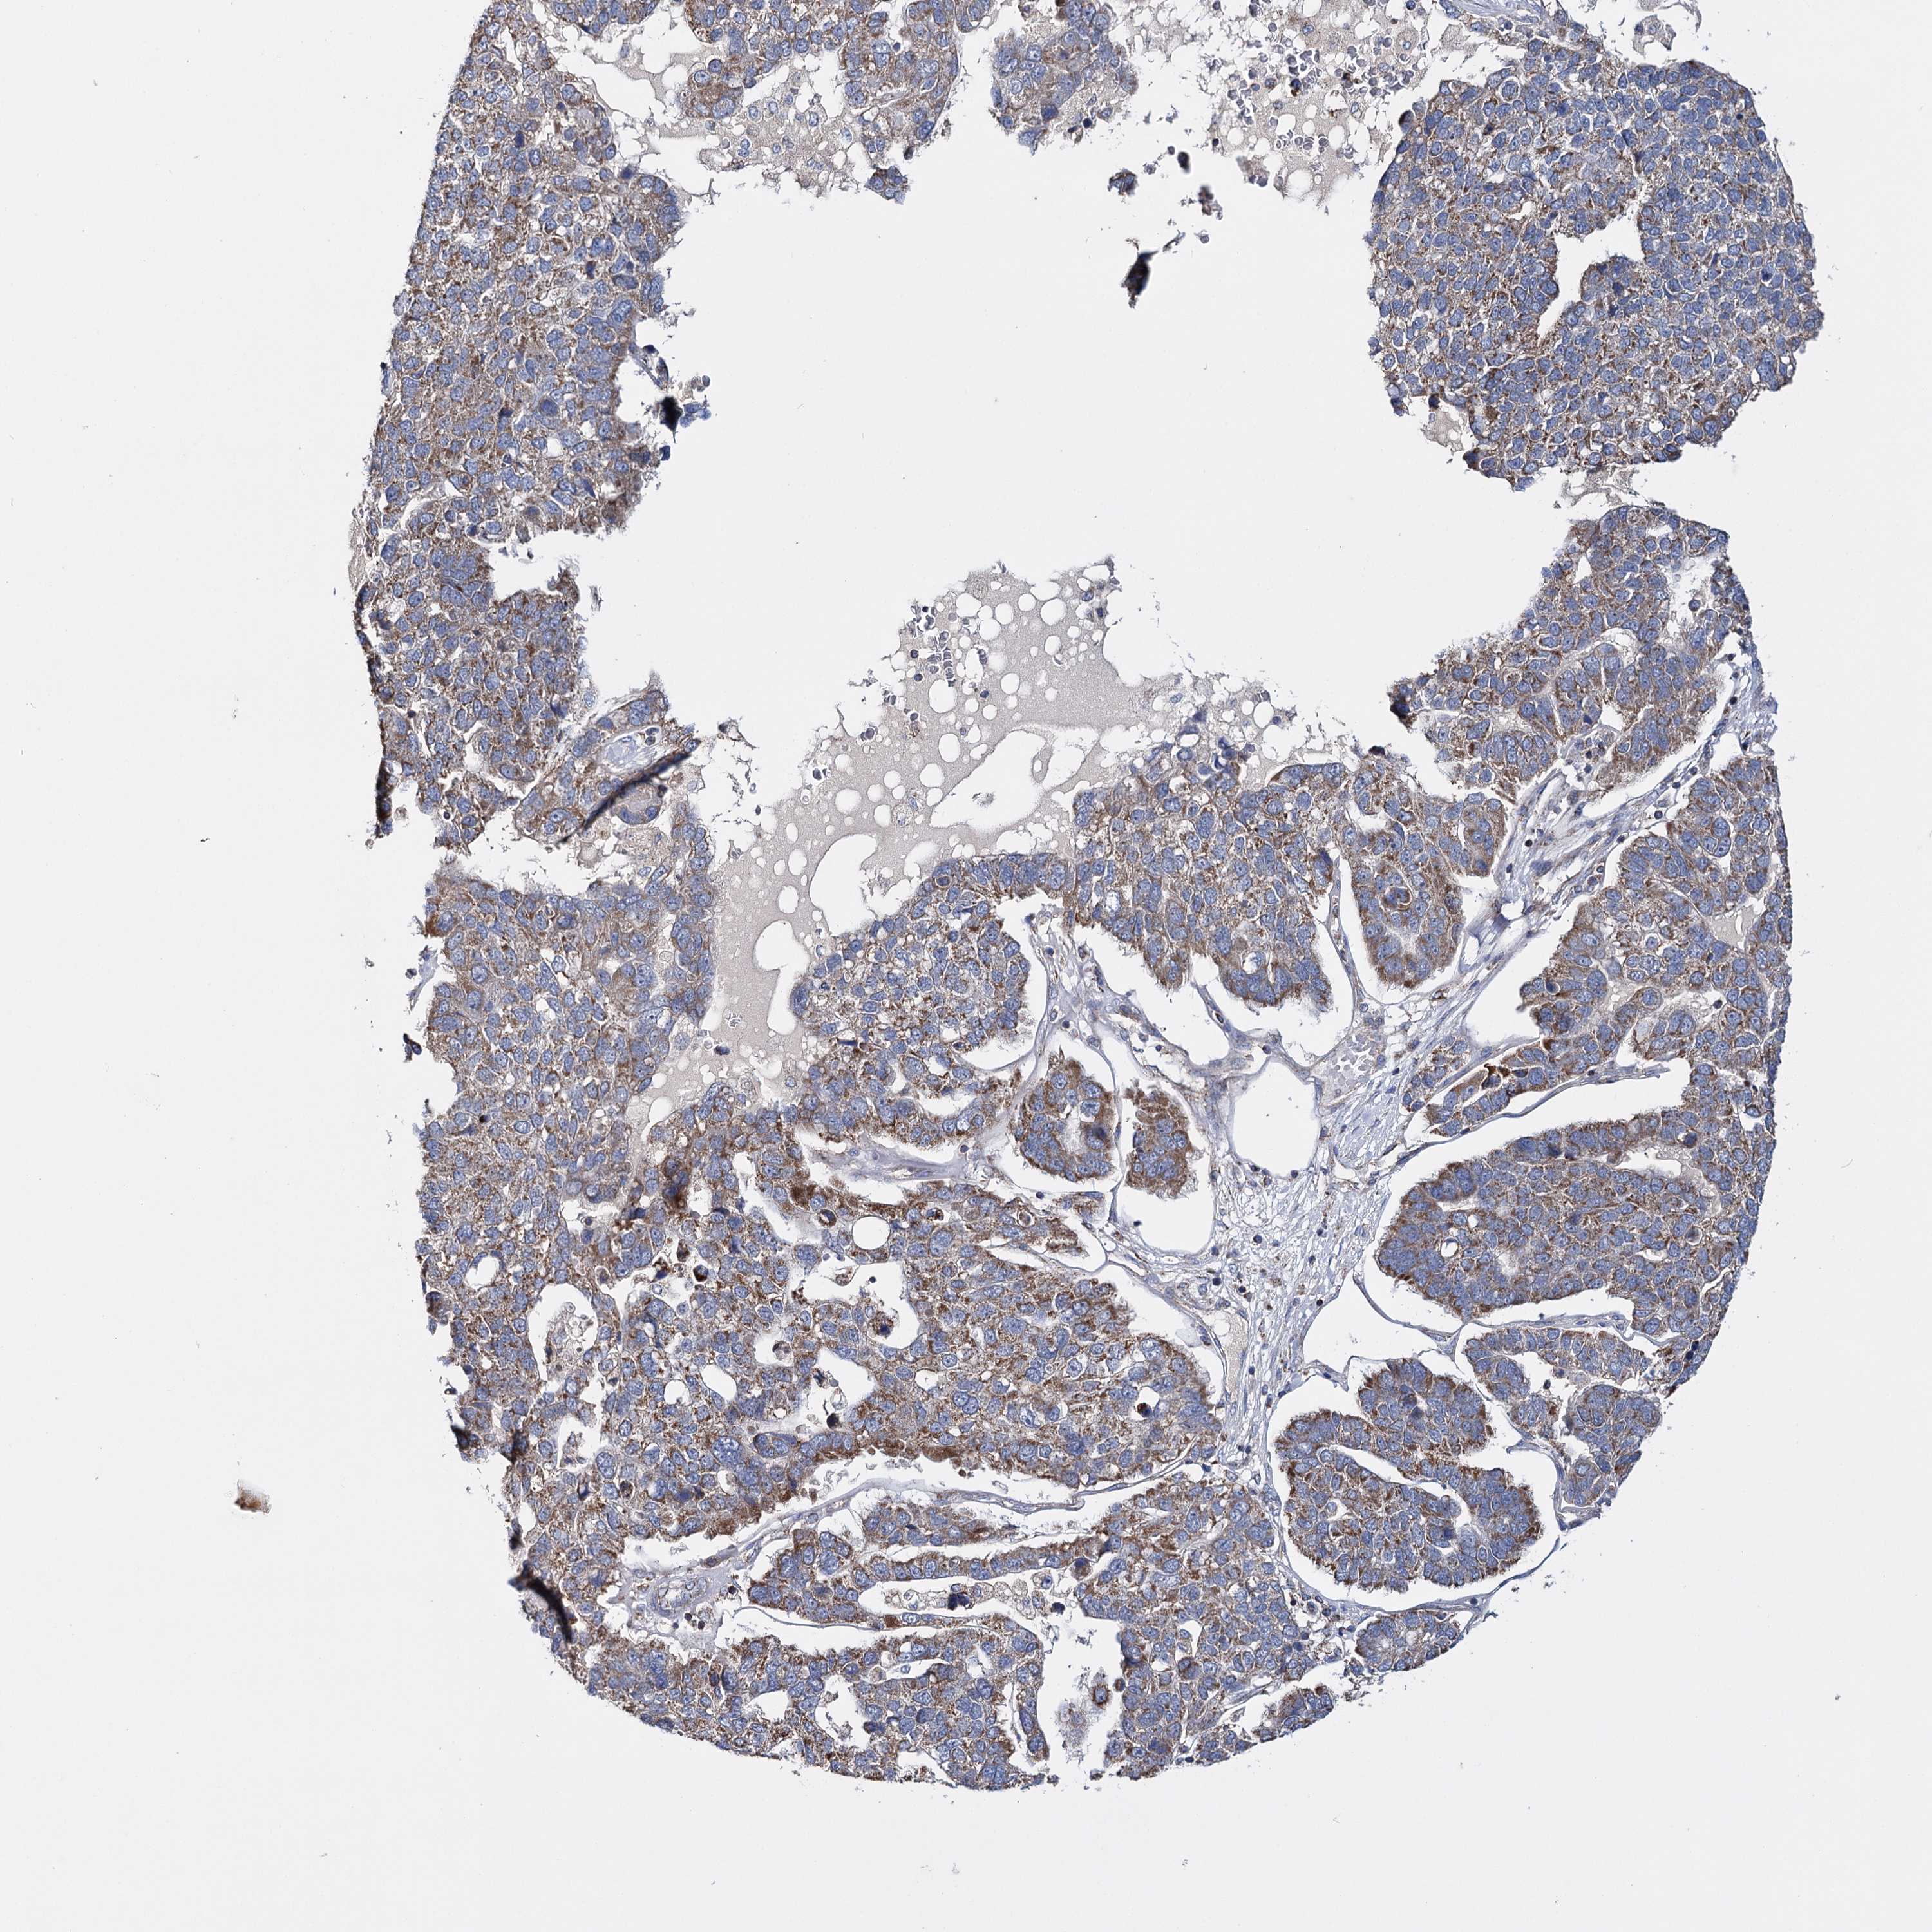

PANCREATIC CANCER - Protein expressioni

A mouse-over function shows sample information and annotation data. Click on an image to view it in a full screen mode. Samples can be filtered based on level of antibody staining by selecting one or several of the following categories: high, medium, low and not detected. The assay and annotation is described here.

Note that samples used for immunohistochemistry by the Human Protein Atlas do not correspond to samples in the TCGA dataset.

Antibody stainingi

Antibody staining in the annotated cell types in the current human tissue is reported as not detected, low, medium, or high, based on conventional immunohistochemistry profiling in selected tissues. This score is based on the combination of the staining intensity and fraction of stained cells.

Each image is clickable and will lead to virtual microscopy that enables deeper exploration of all samples and also displays staining intensity scores, fraction scores and subcellular localization as well as patient and tissue information for each sample.

Antibody HPA037786

Antibody HPA038034

Antibody HPA038867

Antibody HPA038868

Staining

High

Medium

Low

Not detected

Intensity

Strong

Moderate

Weak

Negative

Quantity

>75%

75%-25%

<25%

None

Location

Nuclear

Cytoplasmic/membranous

Cytoplasmic/membranous,nuclear

Adenocarcinoma, NOS